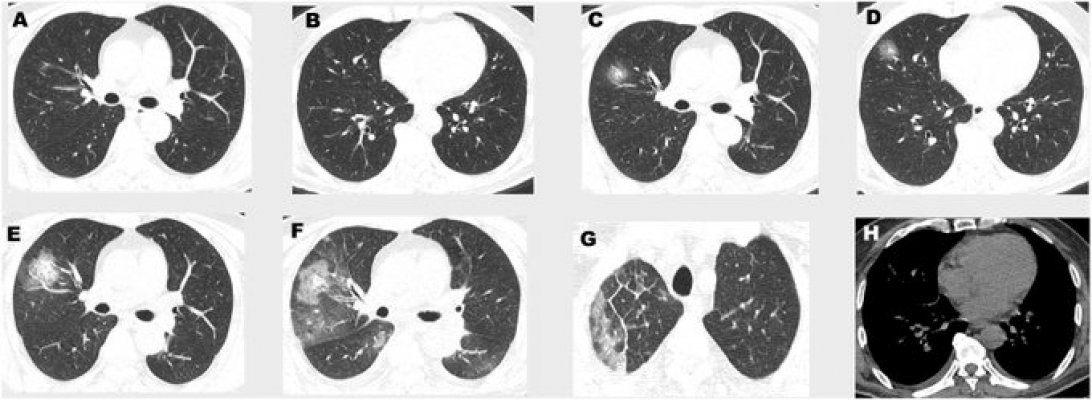

"Neki nemaju simptome, neki dođu sa pregršt problema, ali takođe je istina da ljudi dolaze sa tzv. bilateralnom upalom pluća kada ne možete sami da dišete. Nemamo lijekova, antibiotici ne deluju, tako da im dajemo koktel lijekova koji se koriste protiv virusa poput AIDS, ali ne znamo da li to djeluje ili ne. Sve što možemo je da intubiramo pacijente, da mašina diše umjesto njih, odmorimo pluća i čekamo da imuni sistem pobijedi. Većinu smrtnih slučajeva čine stariji sa već postojećim zdravstvenim problemima, ali ima i mlađih, najmlađi na intenzivnoj njezi ima 38 godina. Nema respiratora za sve. Juče me je neko zvao da im damo jedan respirator, sad imamo samo dva. Ukoliko se pacijentu pogorša stanje, neće biti respiratora. Tako da moramo da odlučimo kome ćemo pomoći, prioritet su mladi i oni bez komorbiditeta. U Nigvardi ne intubiraju starije od 60, što je strašno. Situacija je veoma ozbiljna, veoma je zarazno - 14 dana možete proći bez simptoma, a zaraziti nevejrovatan broj ljudi.